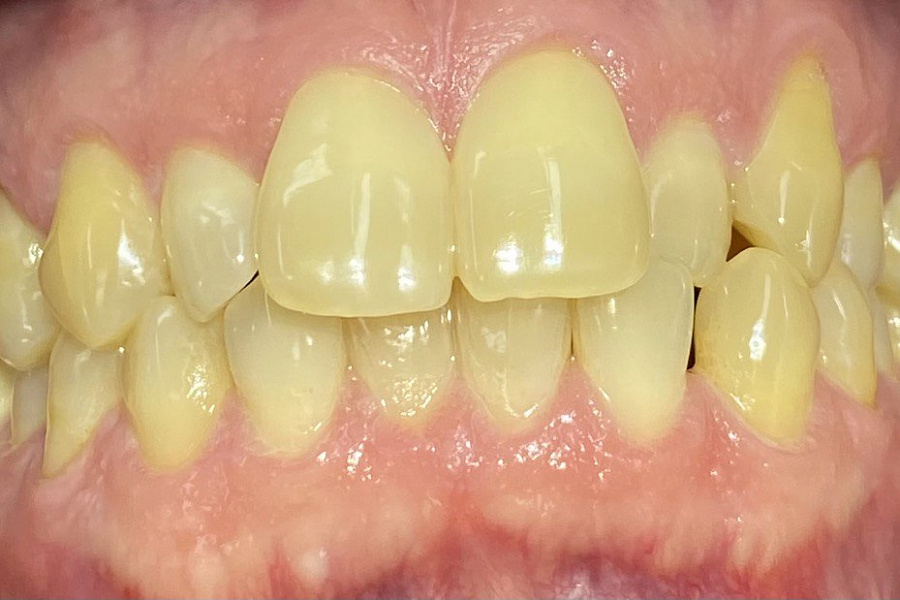

Пациент обратился с жалобами на неровные передние зубы верхней и нижней челюстей.

Диагностика показала:

сужение зубных рядов,

обратное перекрытие в области фронтальных зубов слева,

разворот по оси передних зубов верхней и нижней челюстей,

стираемость эмали зубов,

индивидуальную микродентию 12 и 22 зубов.